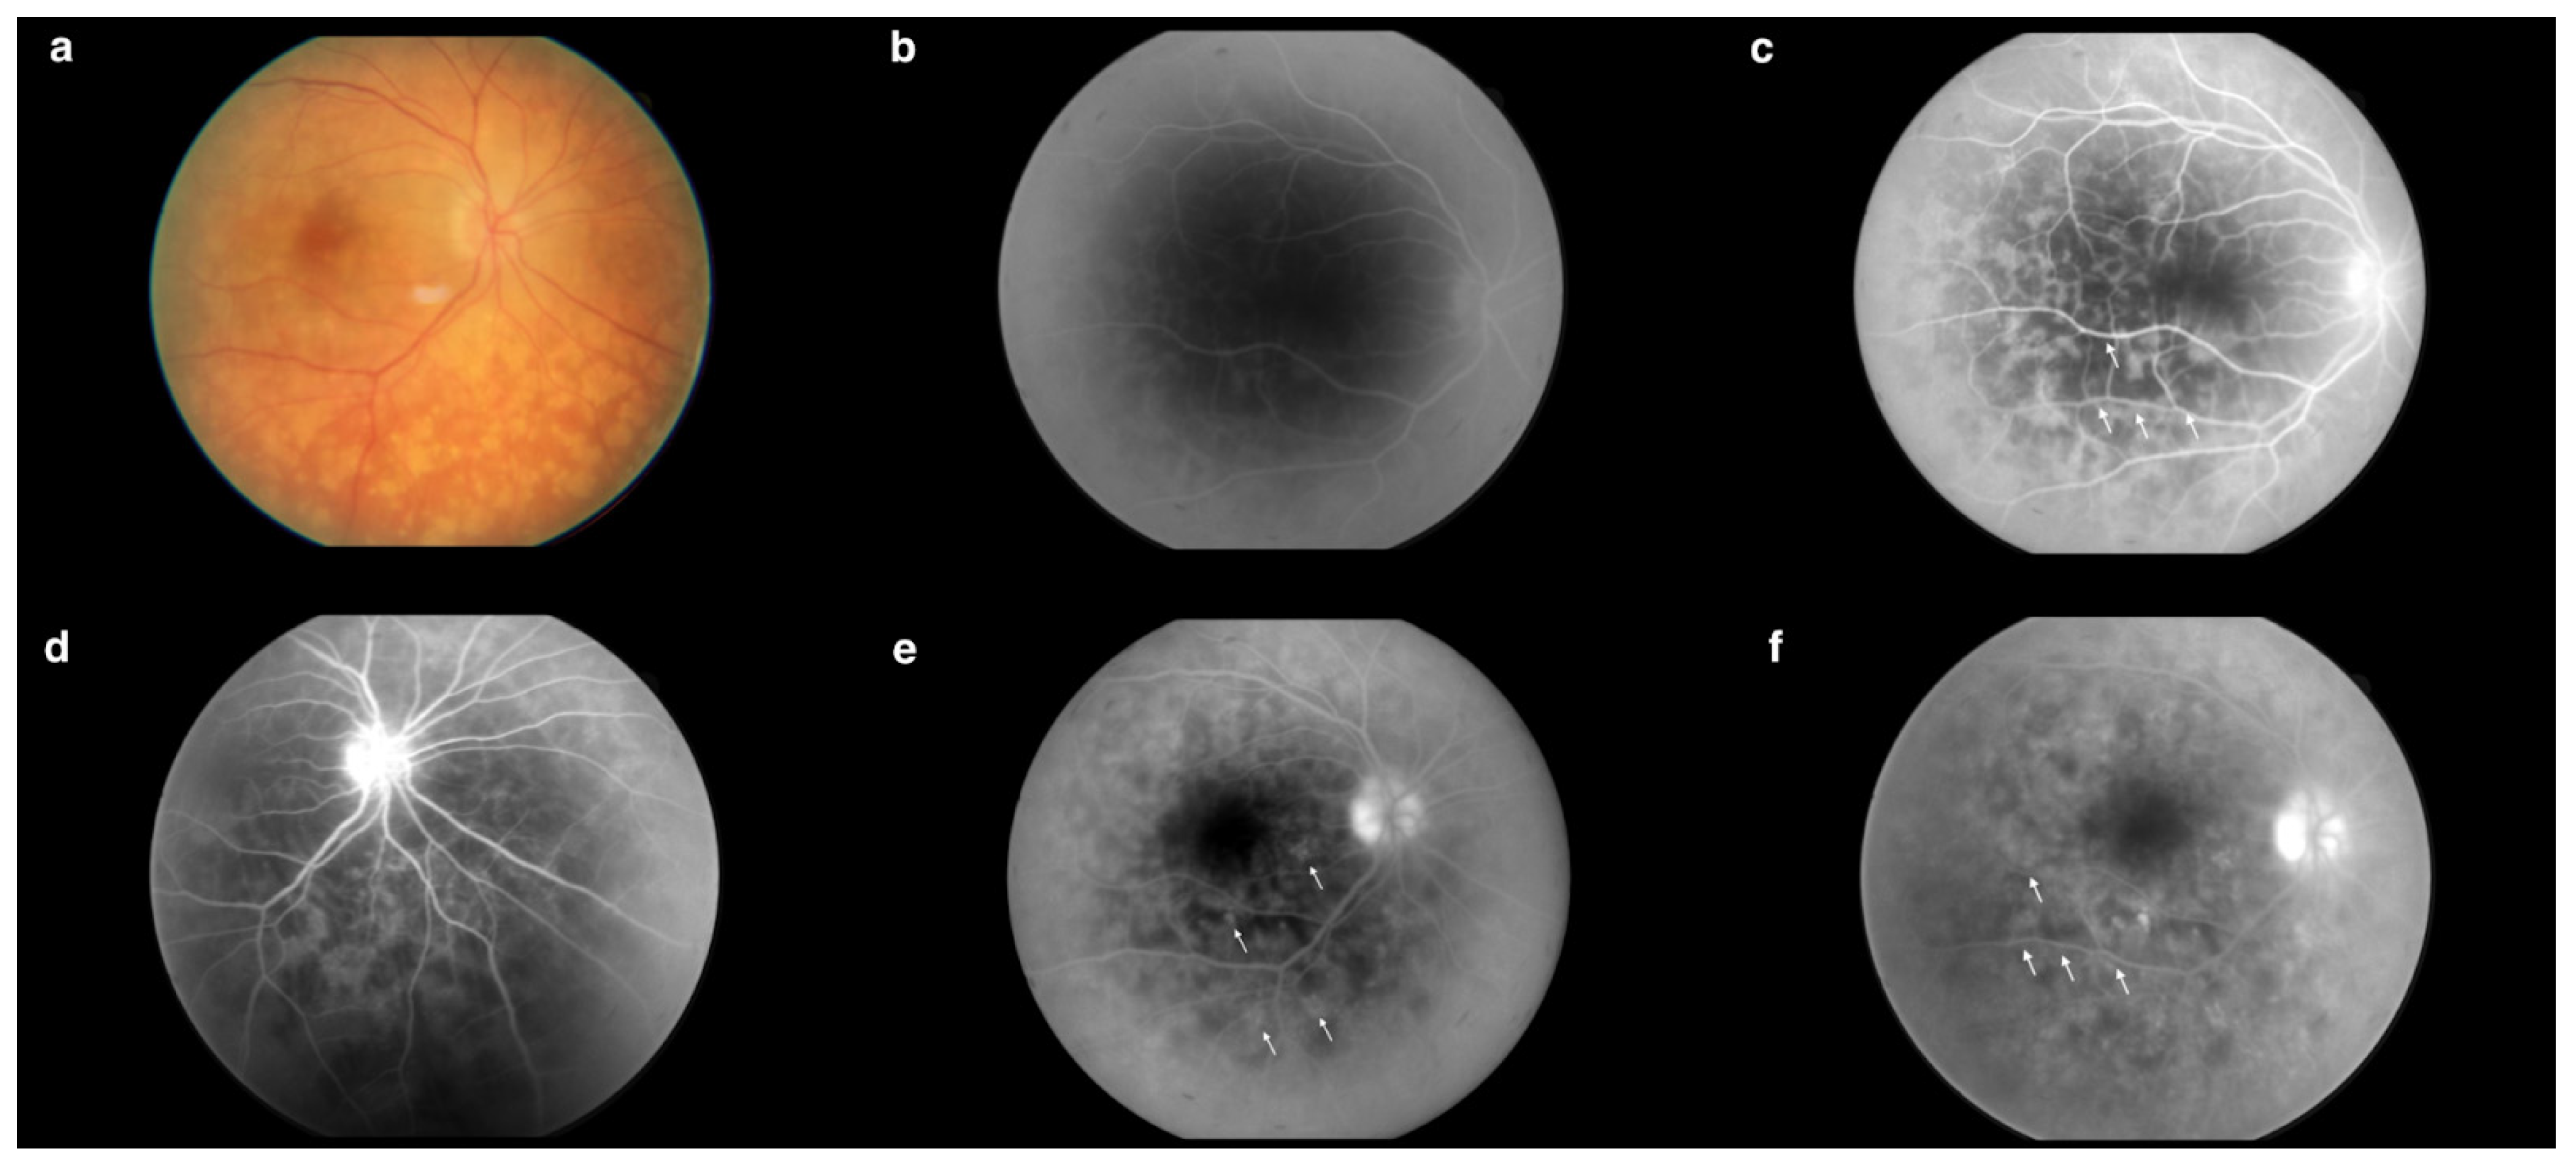

The FA showed significant improvement compared to previous examinations. The regression of the lesions from the periphery was evident as a spotty choroidal structure with lower intensity at the periphery (Figure 14c), occurring mainly in the posterior pole (Figure 14b). Each choroidal lesion in the early phases was hypofluorescent (Figure 14a), while in the later phases each lesion was surrounded by hyperfluorescence (Figure 14d). The fovea remained unchanged; however, there was apparent hyperfluorescence inferiorly and nasally within the FAZ, similar to previous examinations (Figure 14d,e). The FA revealed blurred borders of the optic disc visible from the early phases of the examination (Figure 14a). However, intense hyperfluorescence did not appear until later phases (Figure 14e). Leaks from small vessels were visible, possibly indicative of their inflammation (Figure 14e).

Figure 14.

(a) Hypofluorescent choroidal lesions in early phases. Blurred borders of the optic disc (0′07″). (b) Spotty choroidal structure in the posterior pole (0′20″). (c) Spotty choroidal structure with lower intensity at the periphery (0′25″). (d) Hyperfluorescence inferiorly and nasally within the FAZ. Choroidal lesions surrounded by hyperfluorescence (1′22″). (e) Hyperfluorescence inferiorly and nasally within the FAZ. Intense hyperfluorescence of the optic disc. Leakages from small vessels (4′50″). Examination performed on the 98th day of treatment.